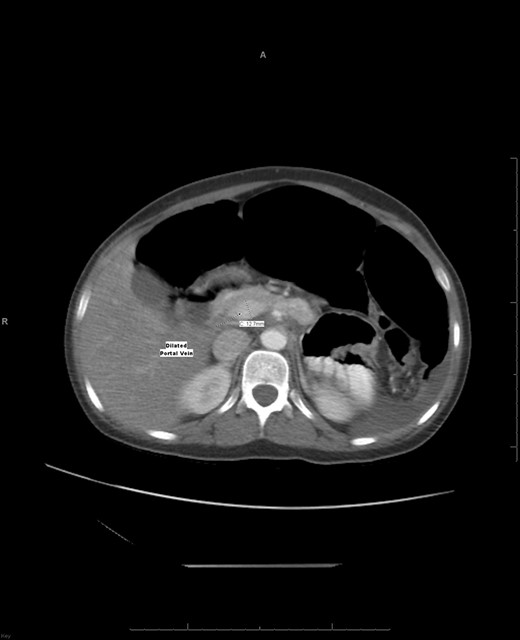

An axial CT shows a widening portal vein 12.7 mm in diameter indicating portal hypertension with multiple dilated portal veins seen at the liver parenchyma.